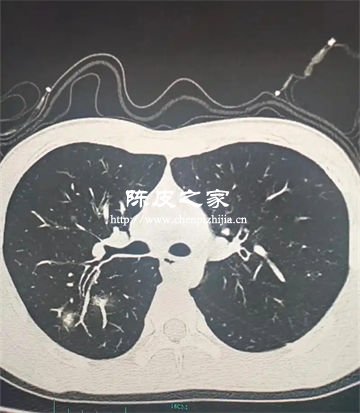

陈皮多糖对PM2.5致肺损伤的防护机制主要体现在抗炎作用、抗氧化应激、抑制气道重塑与纤维化、调节免疫微环境、减少颗粒物沉积与清除等方面。下面进行详细讲解。

PM2.5长期暴露会导致气道杯状细胞增生、黏液高分泌及纤维化,进而引发肺气肿和小气道重塑。陈皮多糖可减少气道黏液分泌,抑制胶原沉积和纤维化进程,缓解PM2.5诱导的气道结构改变。